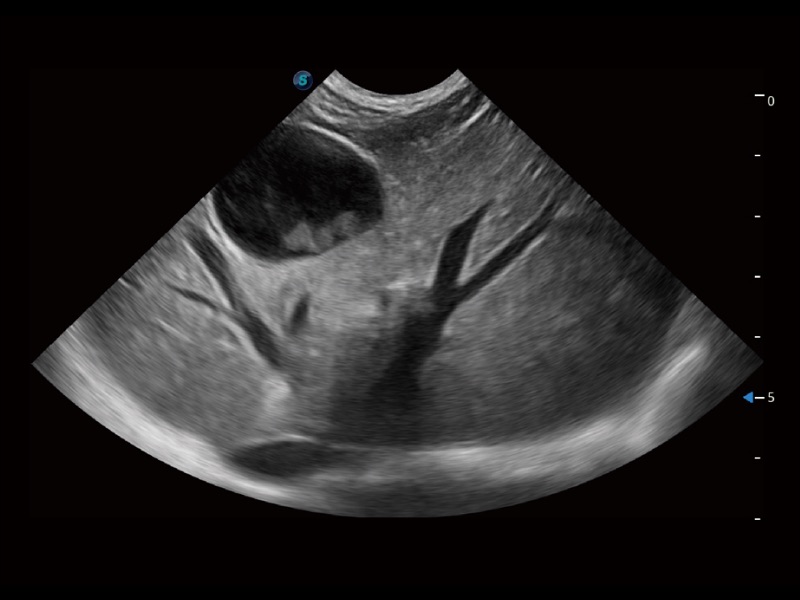

大型犬、马科、农场动物及大型异宠动物

通过创新的 Matrix E自适应滤波器和超长时间域算法,极大提升超低速微细血流的检出能力,同时更精准地滤除软组织和噪声信号,为兽用医生提供以往无法通过常规血流获得的疾病诊断信息。

通过色彩血流和实时宽景相结合,可观察到完整的静脉或动脉的血流,方便医生检查。实时扫查过程中,如有任何操作失误也可以很容易地进行回扫擦除,而不会中断扫查。